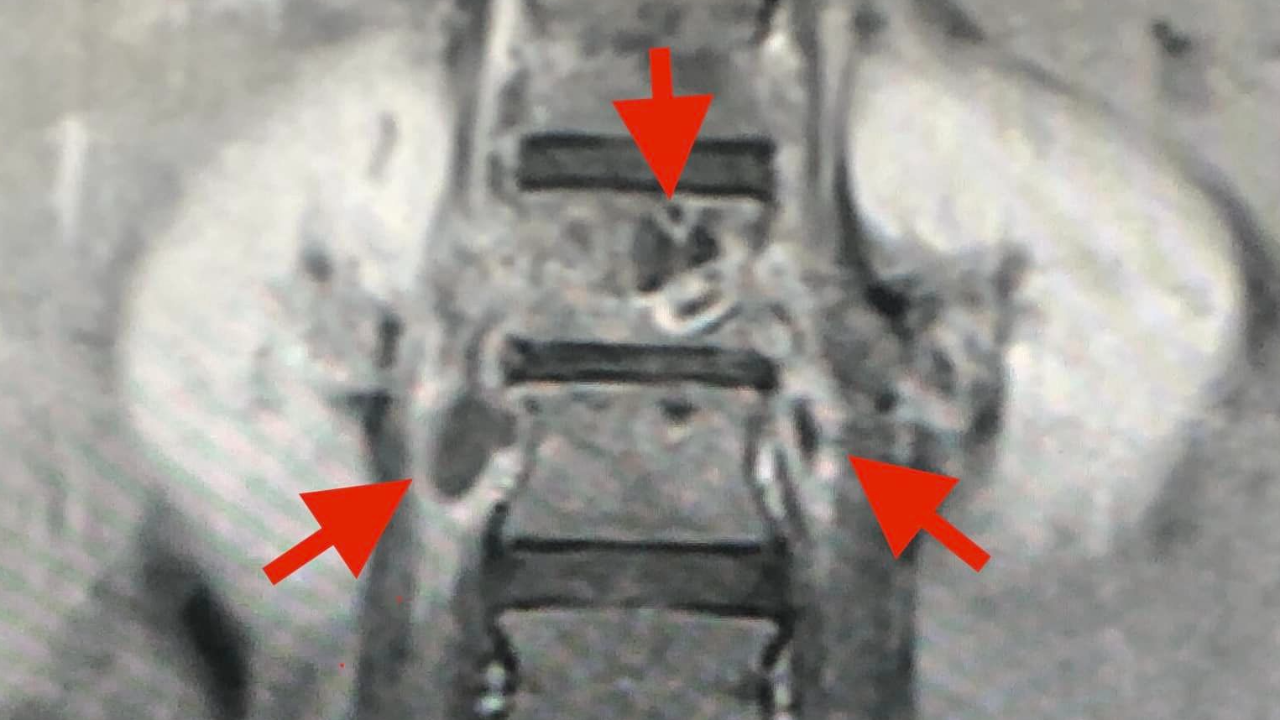

ตรวจร่างกายปกติ เจาะเลือดทุกอย่างปกติ เอกซเรย์ปอดและกระดูกสันหลังส่วนเอวปกติ ทำคลื่นแม่เหล็กไฟฟ้ากระดูกสันหลังส่วนเอว (MRI lumbar spine) ผิดปกติ สงสัยเป็นวัณโรคของกระดูกสันหลังส่วนเอว (lumbar spine) ชิ้นที่หนึ่ง และสงสัยมีการอักเสบรอบๆ เนื้อเยื่อกระดูกสันหลังส่วนเอวชิ้นที่ 1 และ 2 ร่วมด้วย (ดูรูป) ได้ทำการเจาะเนื้อเยื่อรอบกระดูกสันหลังส่วนเอวด้านขวา ส่งตรวจย้อมเชื้อหาวัณโรคให้ผลลบ รอผลเพาะเชื้อวัณโรค ส่งตรวจพยาธิวิทยา ผลมีการตายของเนื้อเยื่อ ไม่พบมะเร็ง